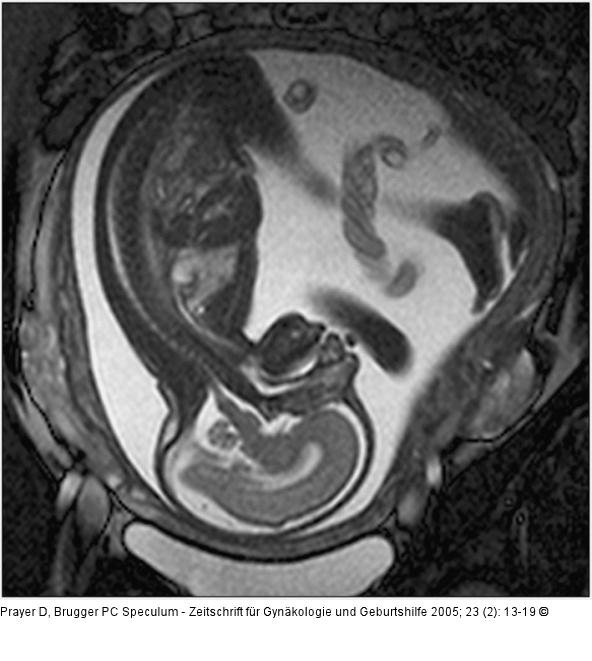

Abbildung 1: Pränatale Magnetresonanztomographie

Sagittale Schichtführung durch einen Fetus in der 27 SSW. Durch das große "Field of View" kann der ganze Fetus abgebildet werden. Das Profil, einschließlich des harten und weichen Gaumens, ist beurteilbar. Intrazerebral erkennt man kortikal den Beginn der Formation der Zentralregion, Hirnstamm und Kleinhirn. Die räumliche Auflösung ist groß genug, um kleine Strukturen wie das Chiasma opticum darzustellen. Intrauterin zeigt sich darüber hinaus eine regelrechte Nabelschnur, die – im Querschnitt getroffen – 3 Gefäße aufweist. |